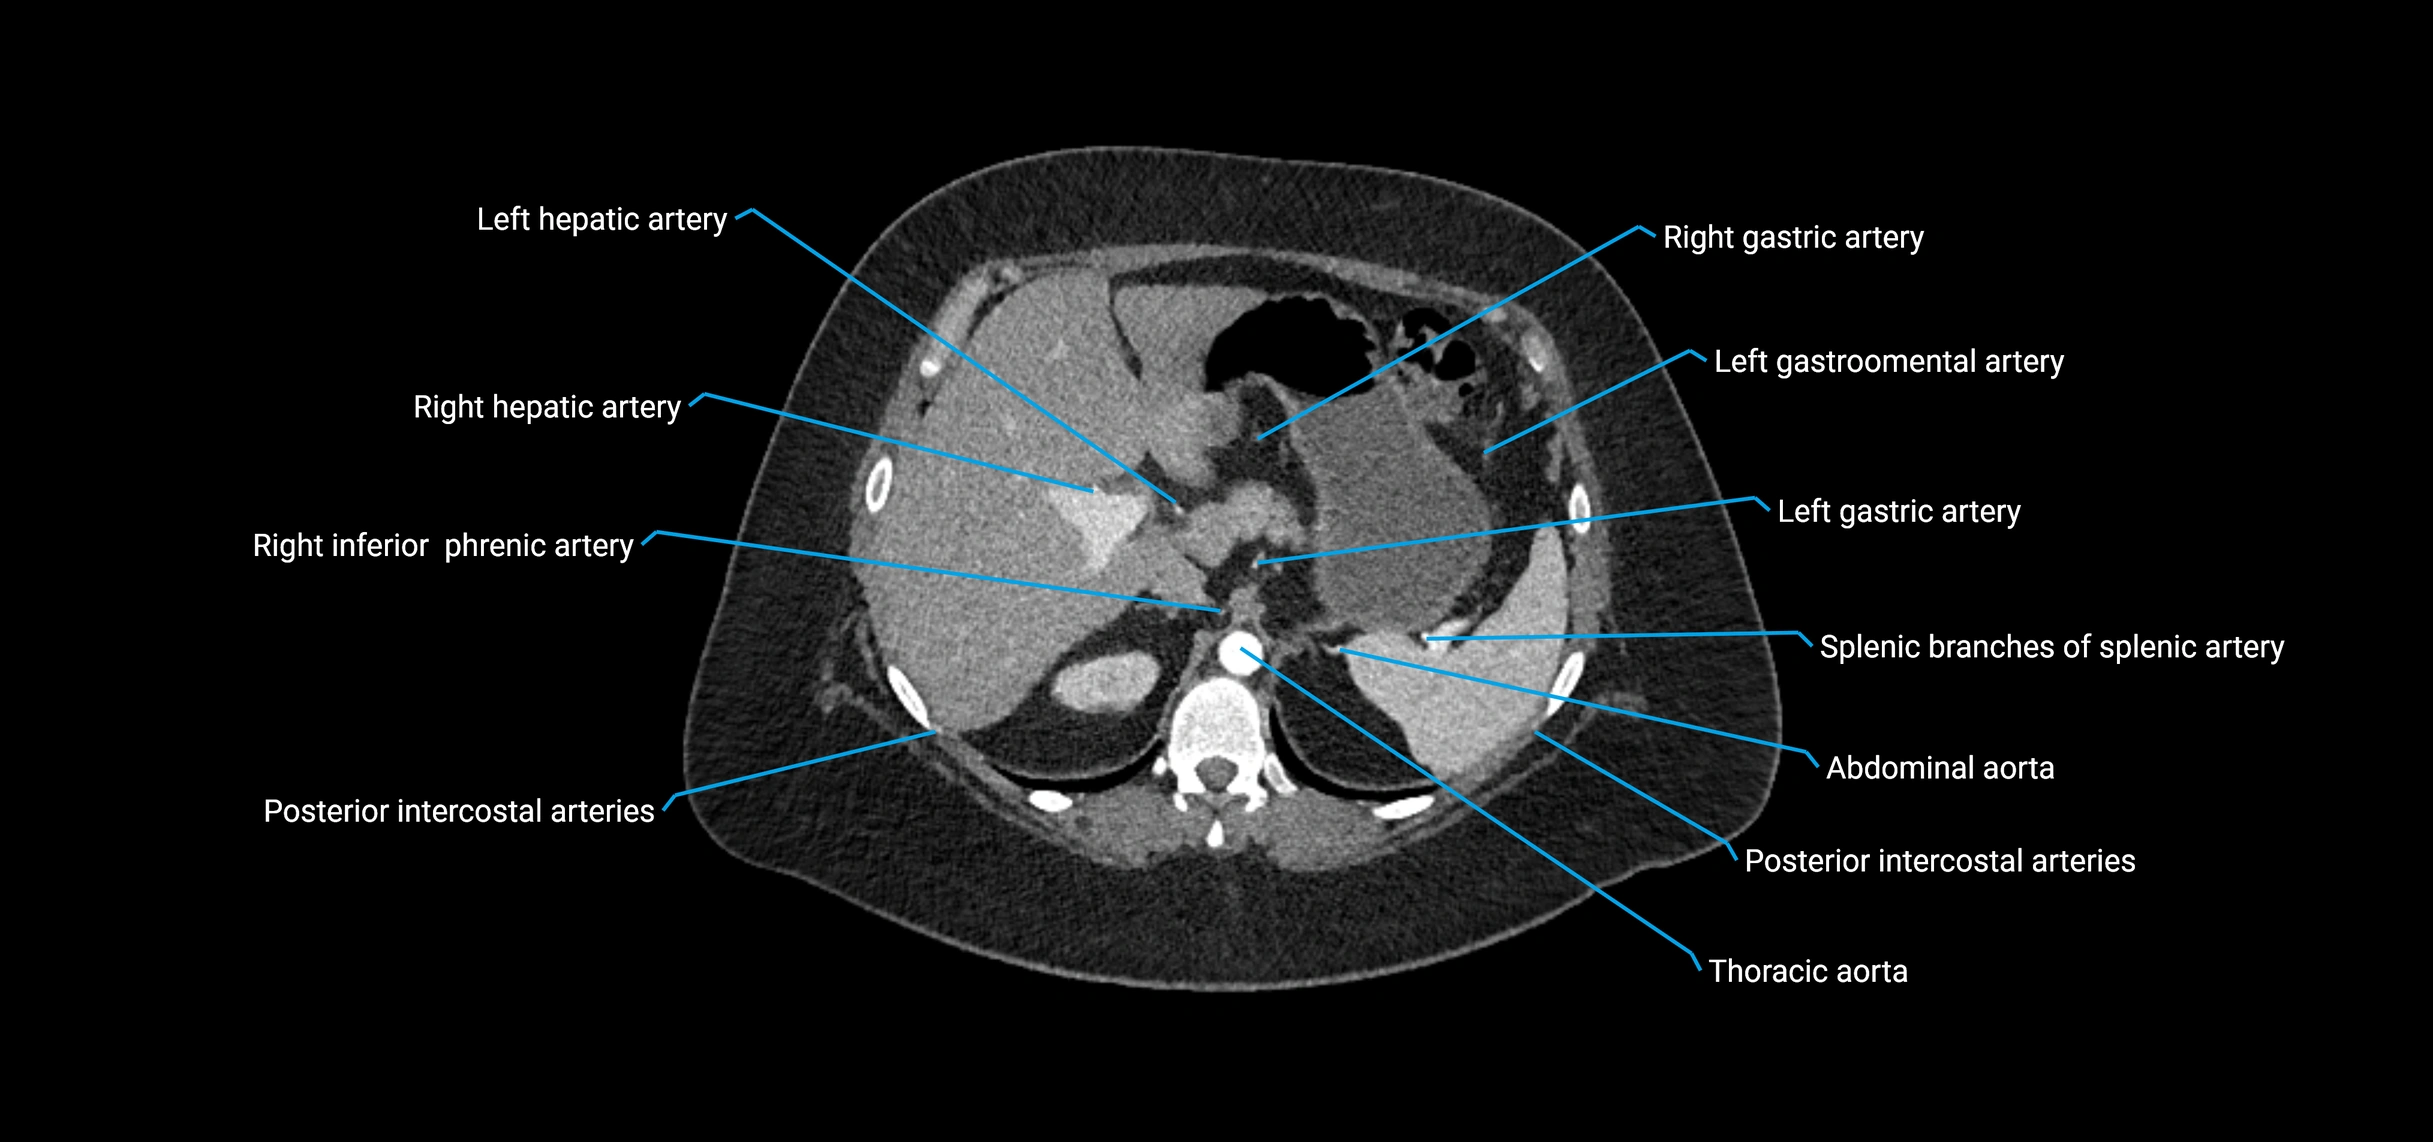

Contrast-enhanced CT (CTA):

• Gold standard for abdominal aortic imaging

• Provides excellent detail of lumen, wall, aneurysm, thrombus, and branch vessels

• Multiplanar and 3D reconstructions help in aneurysm measurement, stent graft planning, and dissection evaluation

• Detects acute rupture, traumatic injury, or occlusion with high sensitivity